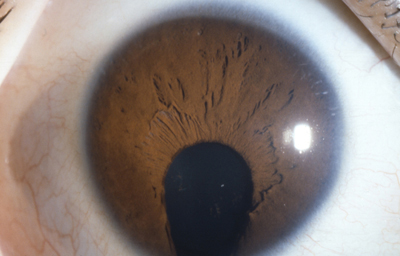

Colobomas típicos con diferentes grados de defecto en el desarrollo

Colobomas Atípicos.

Archivo Fotográfico Dr. Francisco Barraquer

Archivo Fotográfico Dr. Francisco Barraquer